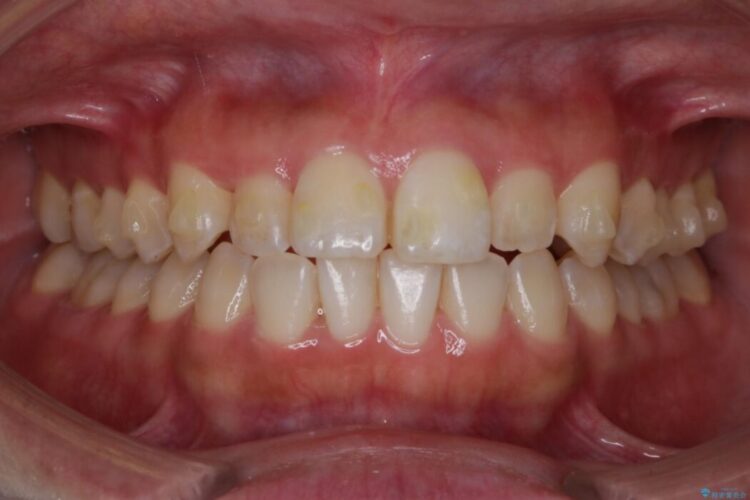

反対咬合の歯も整ったアーチに収まり、きれいに仕上がりました。

今回のケースでは前歯部の軽い凹凸のみであったため部分矯正の適応範囲に該当していました。

適応例は限られますが、部分矯正は全体矯正と比べると矯正期間が短く、費用も安く済みます。